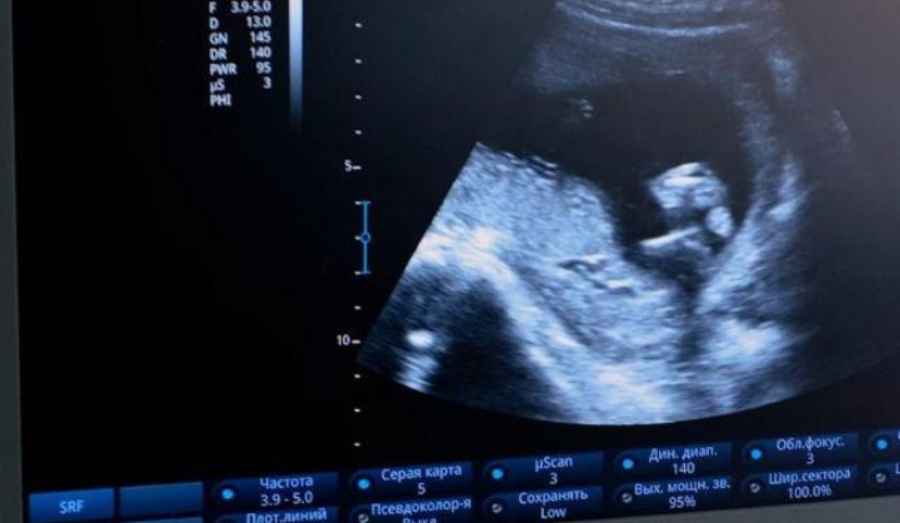

В Новосибирске зафиксирован шокирующий случай, когда 11-летняя девочка стала мамой. Этот инцидент поднимает острые вопросы о сексуальном образовании и ранней половой жизни среди несовершеннолетних. По данным главного репродуктолога Новосибирской области Анны Вятчининой, средний возраст первого полового контакта в регионе составляет 15-16 лет.

Этот показатель значительно отличается от представленной информации о 11-летней роженице. Случай, о котором сообщила заместитель министра здравоохранения Новосибирской области Татьяна Анохина, является исключительным, но тем не менее демонстрирует наличие проблемы. По ее словам, подобные единичные случаи беременности у несовершеннолетних происходят ежегодно, но 11-летний возраст является самым ранним за последнее десятилетие, при этом ребенок родился здоровым.